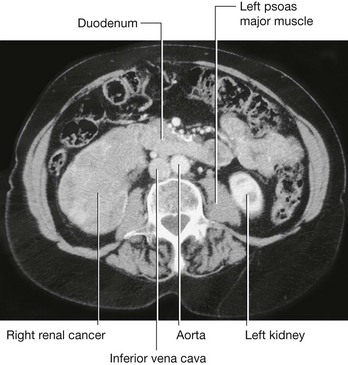

Renal cell tumors are unusual because not only do they grow outward from the kidney, invading the fat and fascia, but they also spread into the renal vein. This venous extension is rare for any other type of tumor, so, when seen, renal cell carcinoma should be suspected. In addition, the tumor may spread along the renal vein and into the inferior vena cava, and in rare cases can grow into the right atrium across the tricuspid valve and into the pulmonary artery (Figs. 4.142 and 4.143).

image

Fig. 4.142 Tumor in the right kidney growing toward, and possibly invading, the duodenum. Computed tomogram in the axial plane.

Fig. 4.143 Tumor in the right kidney spreading into the right renal vein. Computed tomogram in the axial plane.

Treatment for most renal cancers is surgical removal, even when metastatic spread is present, because some patients show regression of metastases.

Transitional cell carcinoma arises from the urothelium. The urothelium is present from the calices to the urethra and behaves as a “single unit.” Therefore, when patients develop transitional carcinomas within the bladder, similar tumors may also be present within upper parts of the urinary tract. In patients with bladder cancer, the whole of the urinary tract must always be investigated to exclude the possibility of other tumors (Fig. 4.144).

Fig. 4.144 Transitional cell carcinoma in the pelvis of the right kidney. Coronal computed tomogram reconstruction.